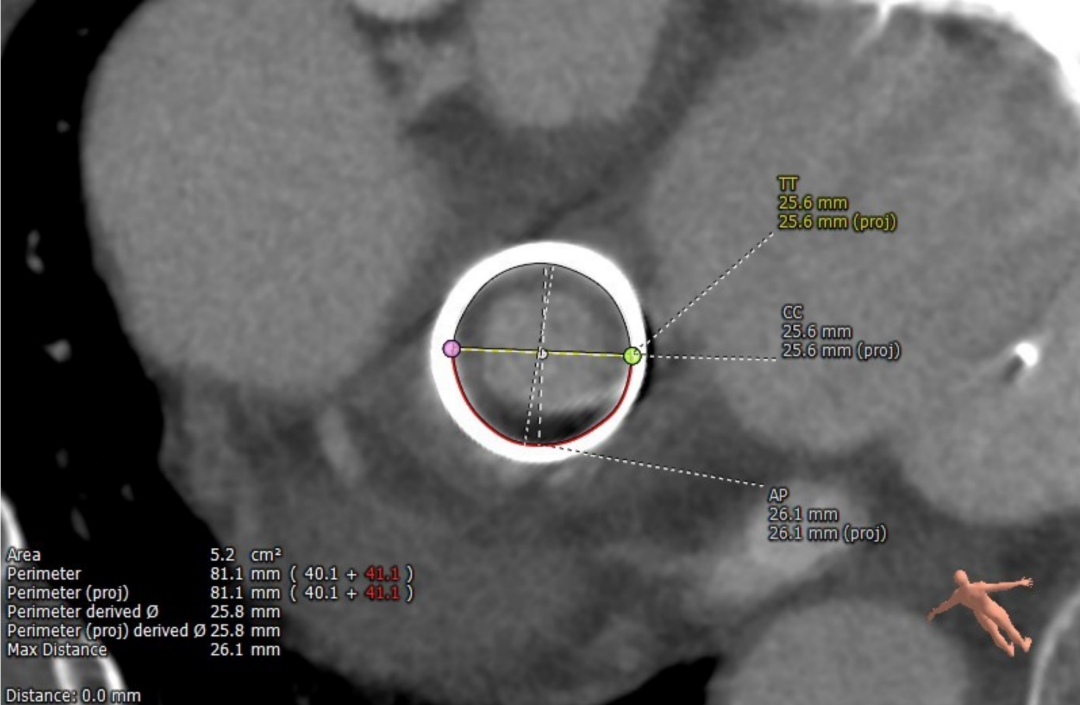

术前经详尽评估患者病情,通过CT重建测量瓣环直径、左室流出道面积。结合之前外科换瓣手术入路,决定采用经心尖途径行二尖瓣“瓣中瓣”手术。术中选用27# Renato®球扩式瓣中瓣,顺利通过心尖途径植入。手术过程顺利,几乎无出血。最终瓣中瓣植入位置理想,功能表现出色,左室造影及经食道超声观察无明显瓣中及瓣周反流。二尖瓣峰值流速由术前2.5m/s降至1.6m/s,平均跨瓣压差由11mmHg降至5mmHg。

毁损生物瓣瓣架结构 瓣环内径测量